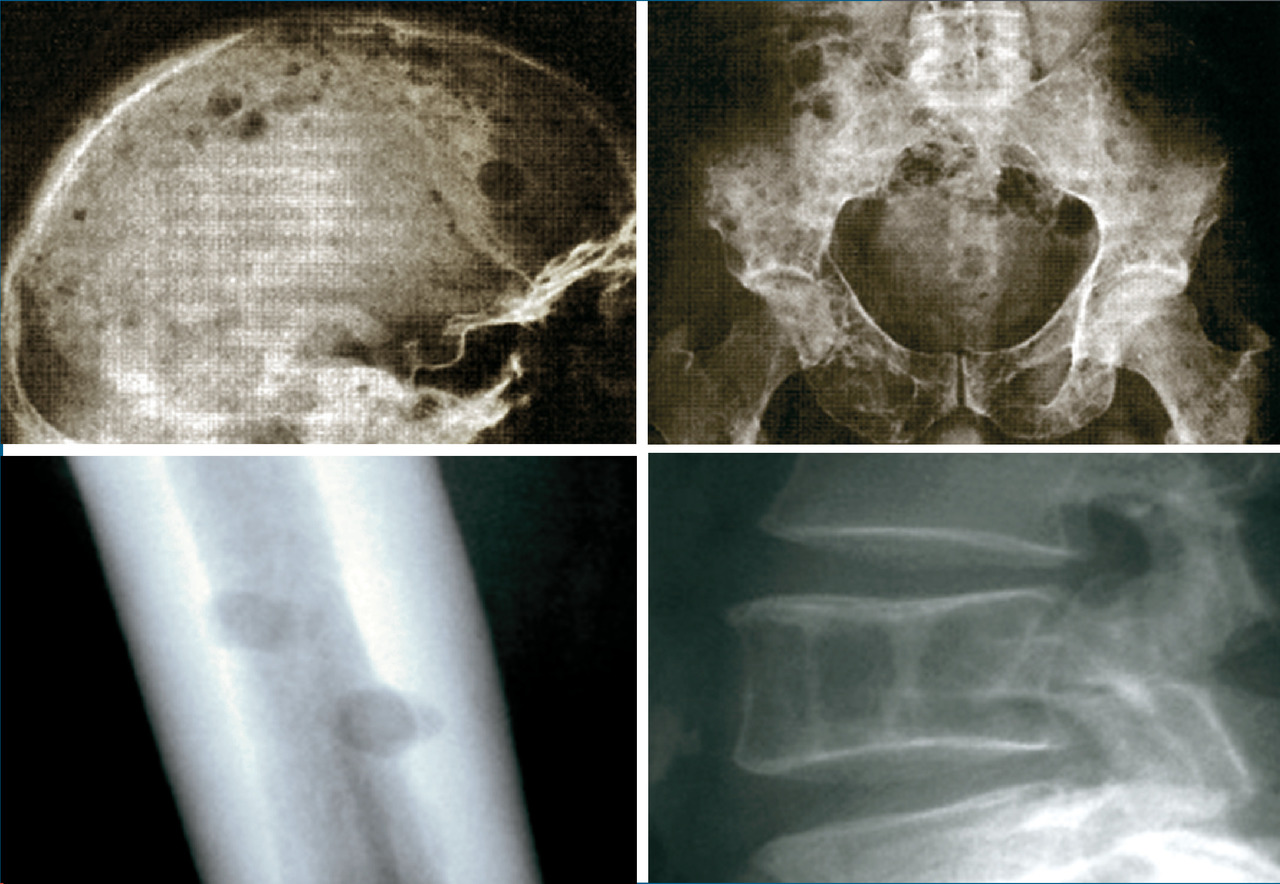

Les plasmocytes myélomateux désorganisent l’homéostasie du stroma médullaire, en activant les ostéoclastes et en inhibant les ostéoblastes. Ce déséquilibre entre résorption et fabrication osseuse conduit à l’apparition de lésions ostéolytiques. Elles sont classiquement « à l’emporte-pièce », principalement dans les os riches en moelle : crâne (fig. 4), rachis, côtes, bassin et os longs (en-deçà des coudes et des genoux, les lésions sont très rares).

Pour compléter les explorations, on demande des radiographies simples des os (pas besoin de scintigraphie osseuse, les lésions du myélome étant peu ou pas fixantes).